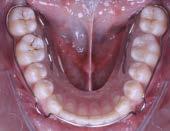

Figura 2. Fotografías oclusales y ortopantomografía. A. Vista de la arcada superior. B. Vista de la arcada inferior. C. Ortopantomografía.

El objetivo de analizar estos conceptos es presentar un caso clínico de paciente masculino de 10 años, clase II división 2, con mordida profunda empleando aparatología ortopédica de Simoes Network y de Pistas Planas.

Reporte de caso clínico

Paciente masculino de 10 años, se presenta a la consulta en la clínica Gnathos, la mamá reporta desagrado en la estética dental y facial del paciente. En la exploración clínica se observa mordida profunda, amplio número de piezas dentales con caries, fracturas dentales, mala higiene y encías inflamadas. presenta clase II división 2, se le indicaron estudios complementarios para diagnóstico asertivo, modelos de estudio,